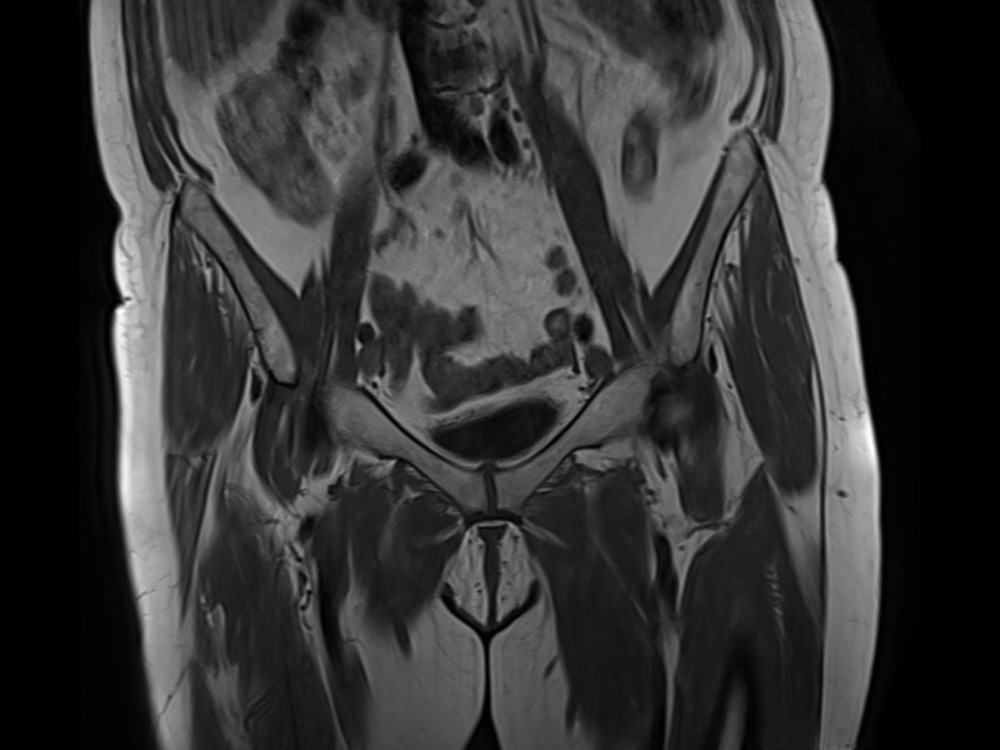

Douleurs de hanche

Linda Ouerd 06/11/2019